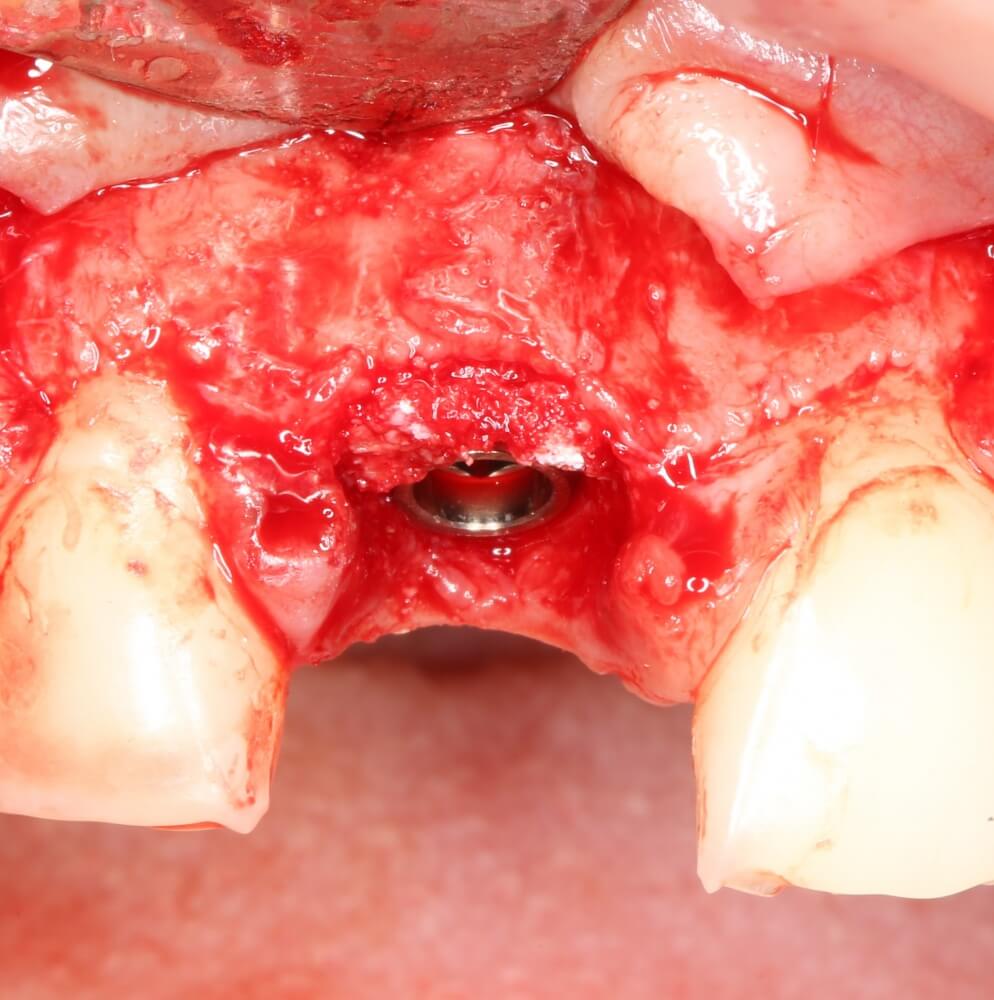

Рекомендации по установке имплантов. Для всех. Часть V.